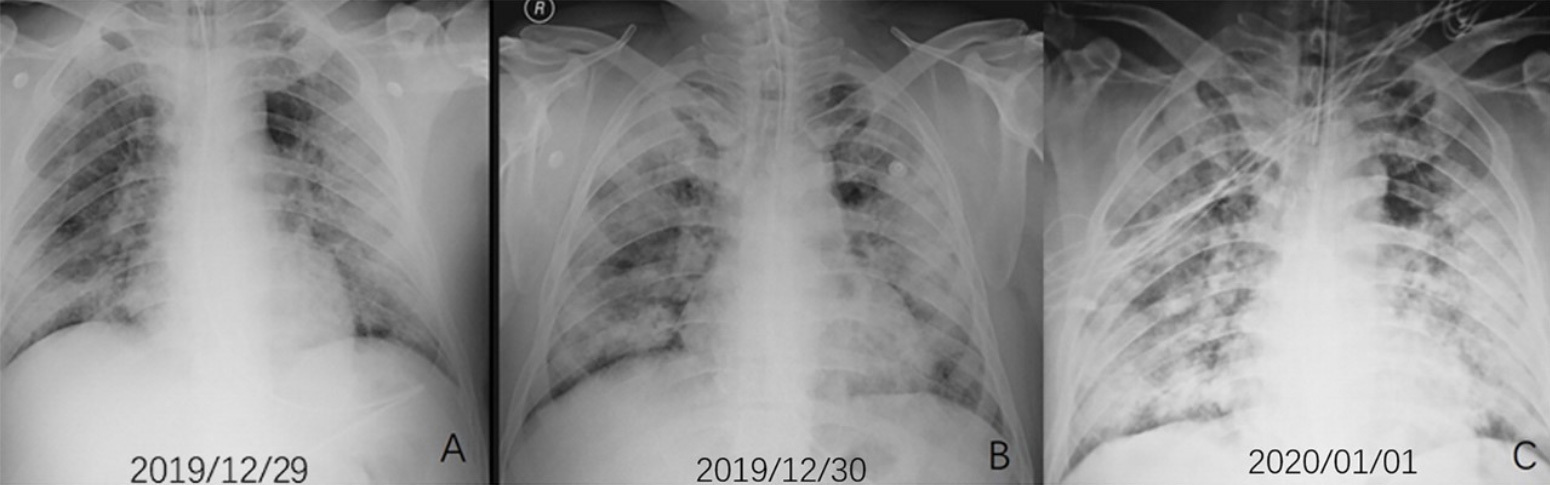

“It’s called acute respiratory distress syndrome, ARDS. That means the lungs are filled with fluid. And it’s notable for the way the X-ray looks: The entire lung is basically whited out from fluid. Patients with ARDS are extremely difficult to oxygenate. It has a really high mortality rate, about 40%. The way to manage it is to put a patient on a ventilator. The additional pressure helps the oxygen go into the bloodstream.

“Typically with ARDS, the lungs become inflamed. It’s like inflammation anywhere: If you have a burn on your arm, the skin around it turns red from additional blood flow. The body is sending it additional nutrients to heal. The problem is, when that happens in your lungs, fluid and extra blood starts going to the lungs. Viruses can injure cells in the walls of the alveoli, so the fluid leaks into the alveoli. A telltale sign of ARDS in an X-ray is what’s called ‘ground glass opacity,’ like an old-fashioned ground glass privacy window in a shower. And lungs look that way because fluid is white on an X-ray, so the lung looks like white ground glass, or sometimes pure white, because the lung is filled with so much fluid, displacing where the air would normally be.”